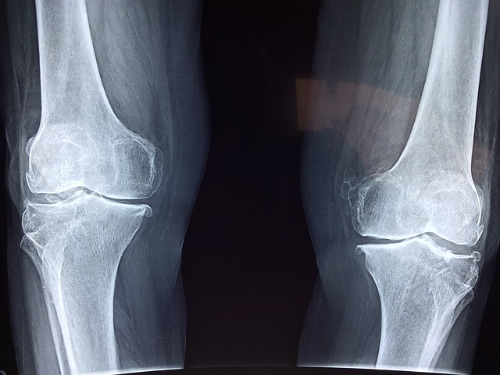

나이가 들면서 찾아오는 퇴행성 관절염은 불편함과 통증으로 일상생활에 지장을 줄 수 있습니다. 오늘은 관절에 좋다고 알려진 '오스테민 캡슐'에 대해 이야기해보려 합니다. 특히 오스테민 캡슐의 성분, 효능, 그리고 관절염에 대한 효과, 복용법에 초점을 맞춰서 설명하도록 하겠습니다.

오스테민 캡슐은 경증에서 중등도의 골(뼈)관절염(퇴행성관절염)에 효과가 있다고 알려져 있습니다. 특히 오스테민 캡슐은 비스테로이드성 소염진통제와 달리 Prostaglandin의 생합성을 억제하지 않고 항염작용을 나타내므로, 위장장애 등의 부작용이 개선되어 장기간 치료에 적합합니다.

4. 오스테민 캡슐 관절염